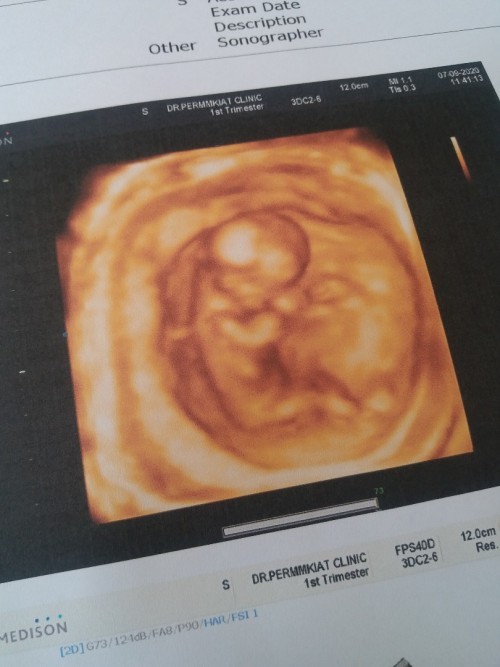

13วีคคร่า